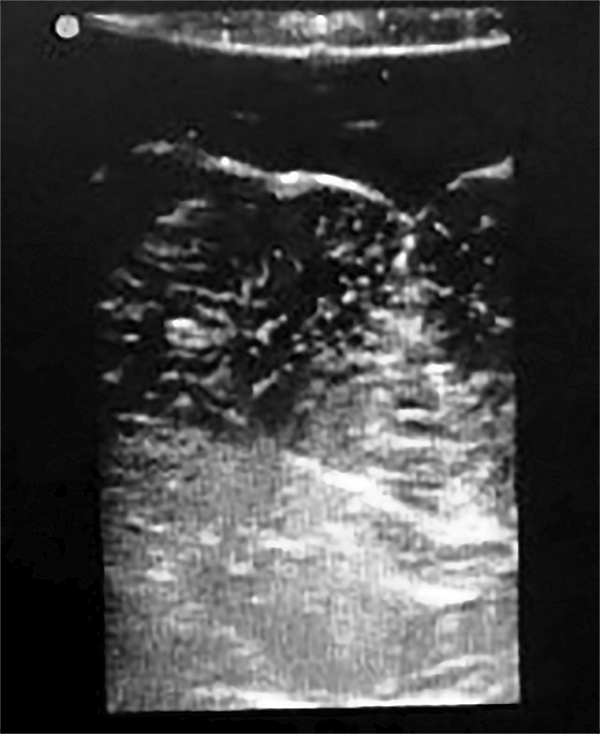

A los 29 meses de edad se realizó una exéresis subtotal de la lesión a través de un abordaje suboccipital telovelar (fig. 4). Durante el procedimiento se realizó elecrocorticografía (ECoG), con un electrodo profundo colocado bajo guía ecográfica intraoperatoria que no mostró patrones patológicos. La experiencia en ECoG cerebelosa es escala o nula, por lo tanto se hace muy difícil su interpretación(fig. 5).

Figura 4: Caso 2. Ecografia intraoperatoria.